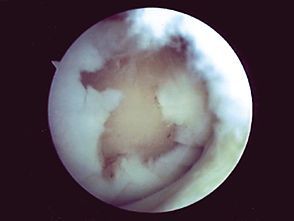

Technique Les greffes osteo-chondrales selon la technique de la mosaicplasty , P. Christel Clinique Nollet, 75017 PARIS - , G. Versier Hôpital Begin - Saint-Mandé, , Philippe Landreau Clinique des Lilas, 93260 Les Lilas, France , Patrick Djian Clinique Chantereine, 77177 Brou Sur Chantereine, France N°76 - Septembre 1998 ● 26 min de lecture